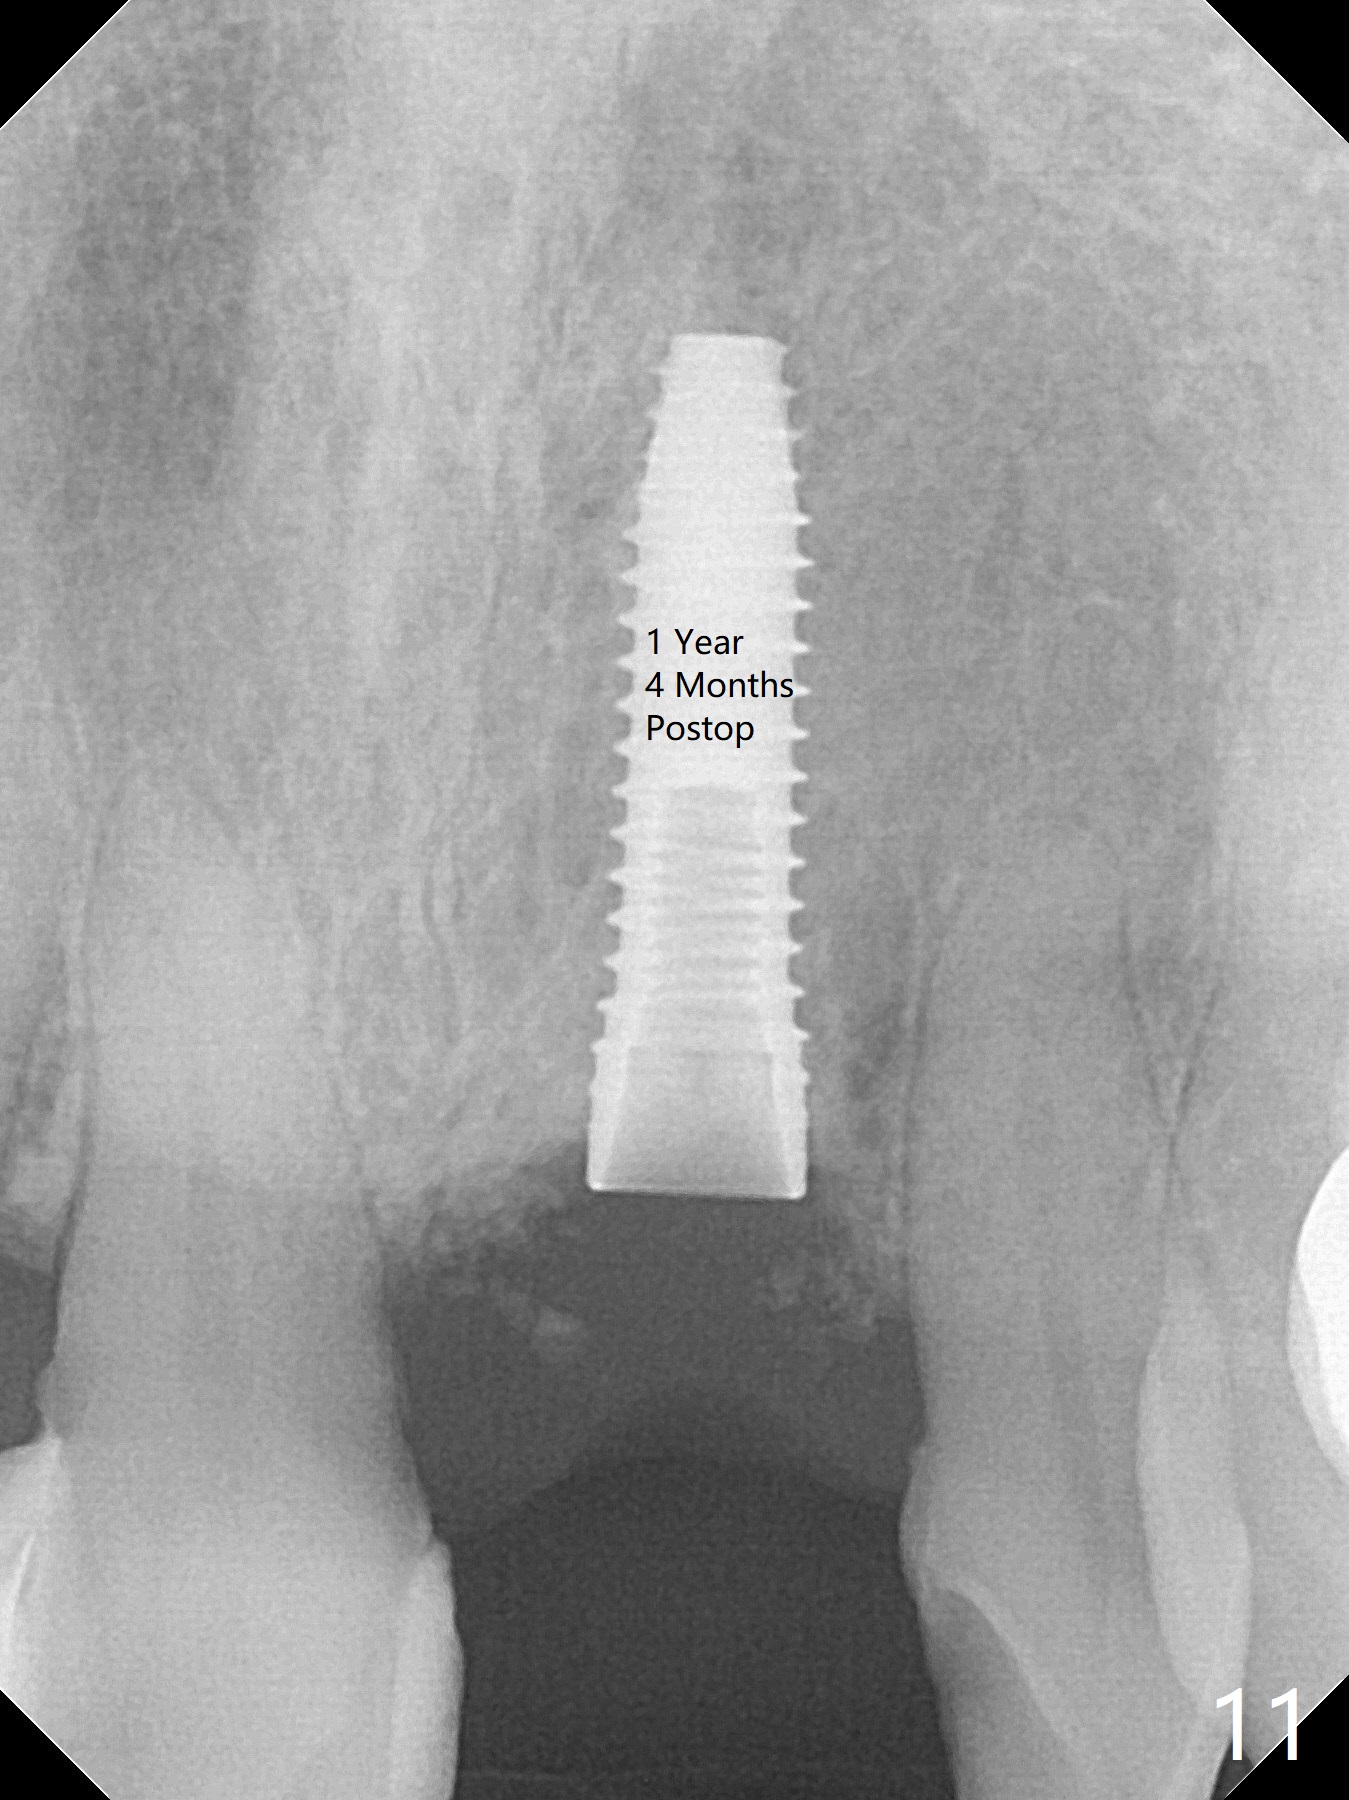

In spite of the incisobuccal shift of the tooth #9 with gingival recession (Fig.1) and loss of the buccal plate (intraop finding), there is no buccal contour collapse (Fig.2 *), due to the presence of the buccal bone of the neighboring teeth and the root of the affected tooth. After extraction, osteotomy (Fig.3) and dummy implant try in (Fig.4), a definitive implant is placed palatally with the buccal gap (Fig.5 *). In fact there is mild buccal contour collapse prior to bone graft (Fig.5 arrow). When allograft (Vera, Fig.6,7 *) is packed buccal to the implant and overlying abutment as a solid support, the buccal contour seemingly returns normal (Fig.6 arrowhead). An immediate provisional is fabricated to prevent loss of the bone graft during healing period. Bone graft kept in place by the provisional turns yellow 6 days postop (Fig.8). The buccal plate remains strong, while the fistula becomes indistinguishable. After adjustment of the provisional margin a few times (nearly 3 months postop, Fig.9,10), the gingival margin appears to have grown incisally, as compared to Fig.1. There is minimal buccal bone collapse (Fig.10). Dislodgement of the abutment and provisional forces her to return 1 year 4 months postop; the socket has healed (Fig.11). The buccal plate is not concave 1 year 4 months postop (Fig.12). The gingiva is slightly recessive (Fig.13) with mild buccal plate concavity (Fig.14) immediately before cementation. The implant could be placed ~ 1 mm deeper (Fig.15).